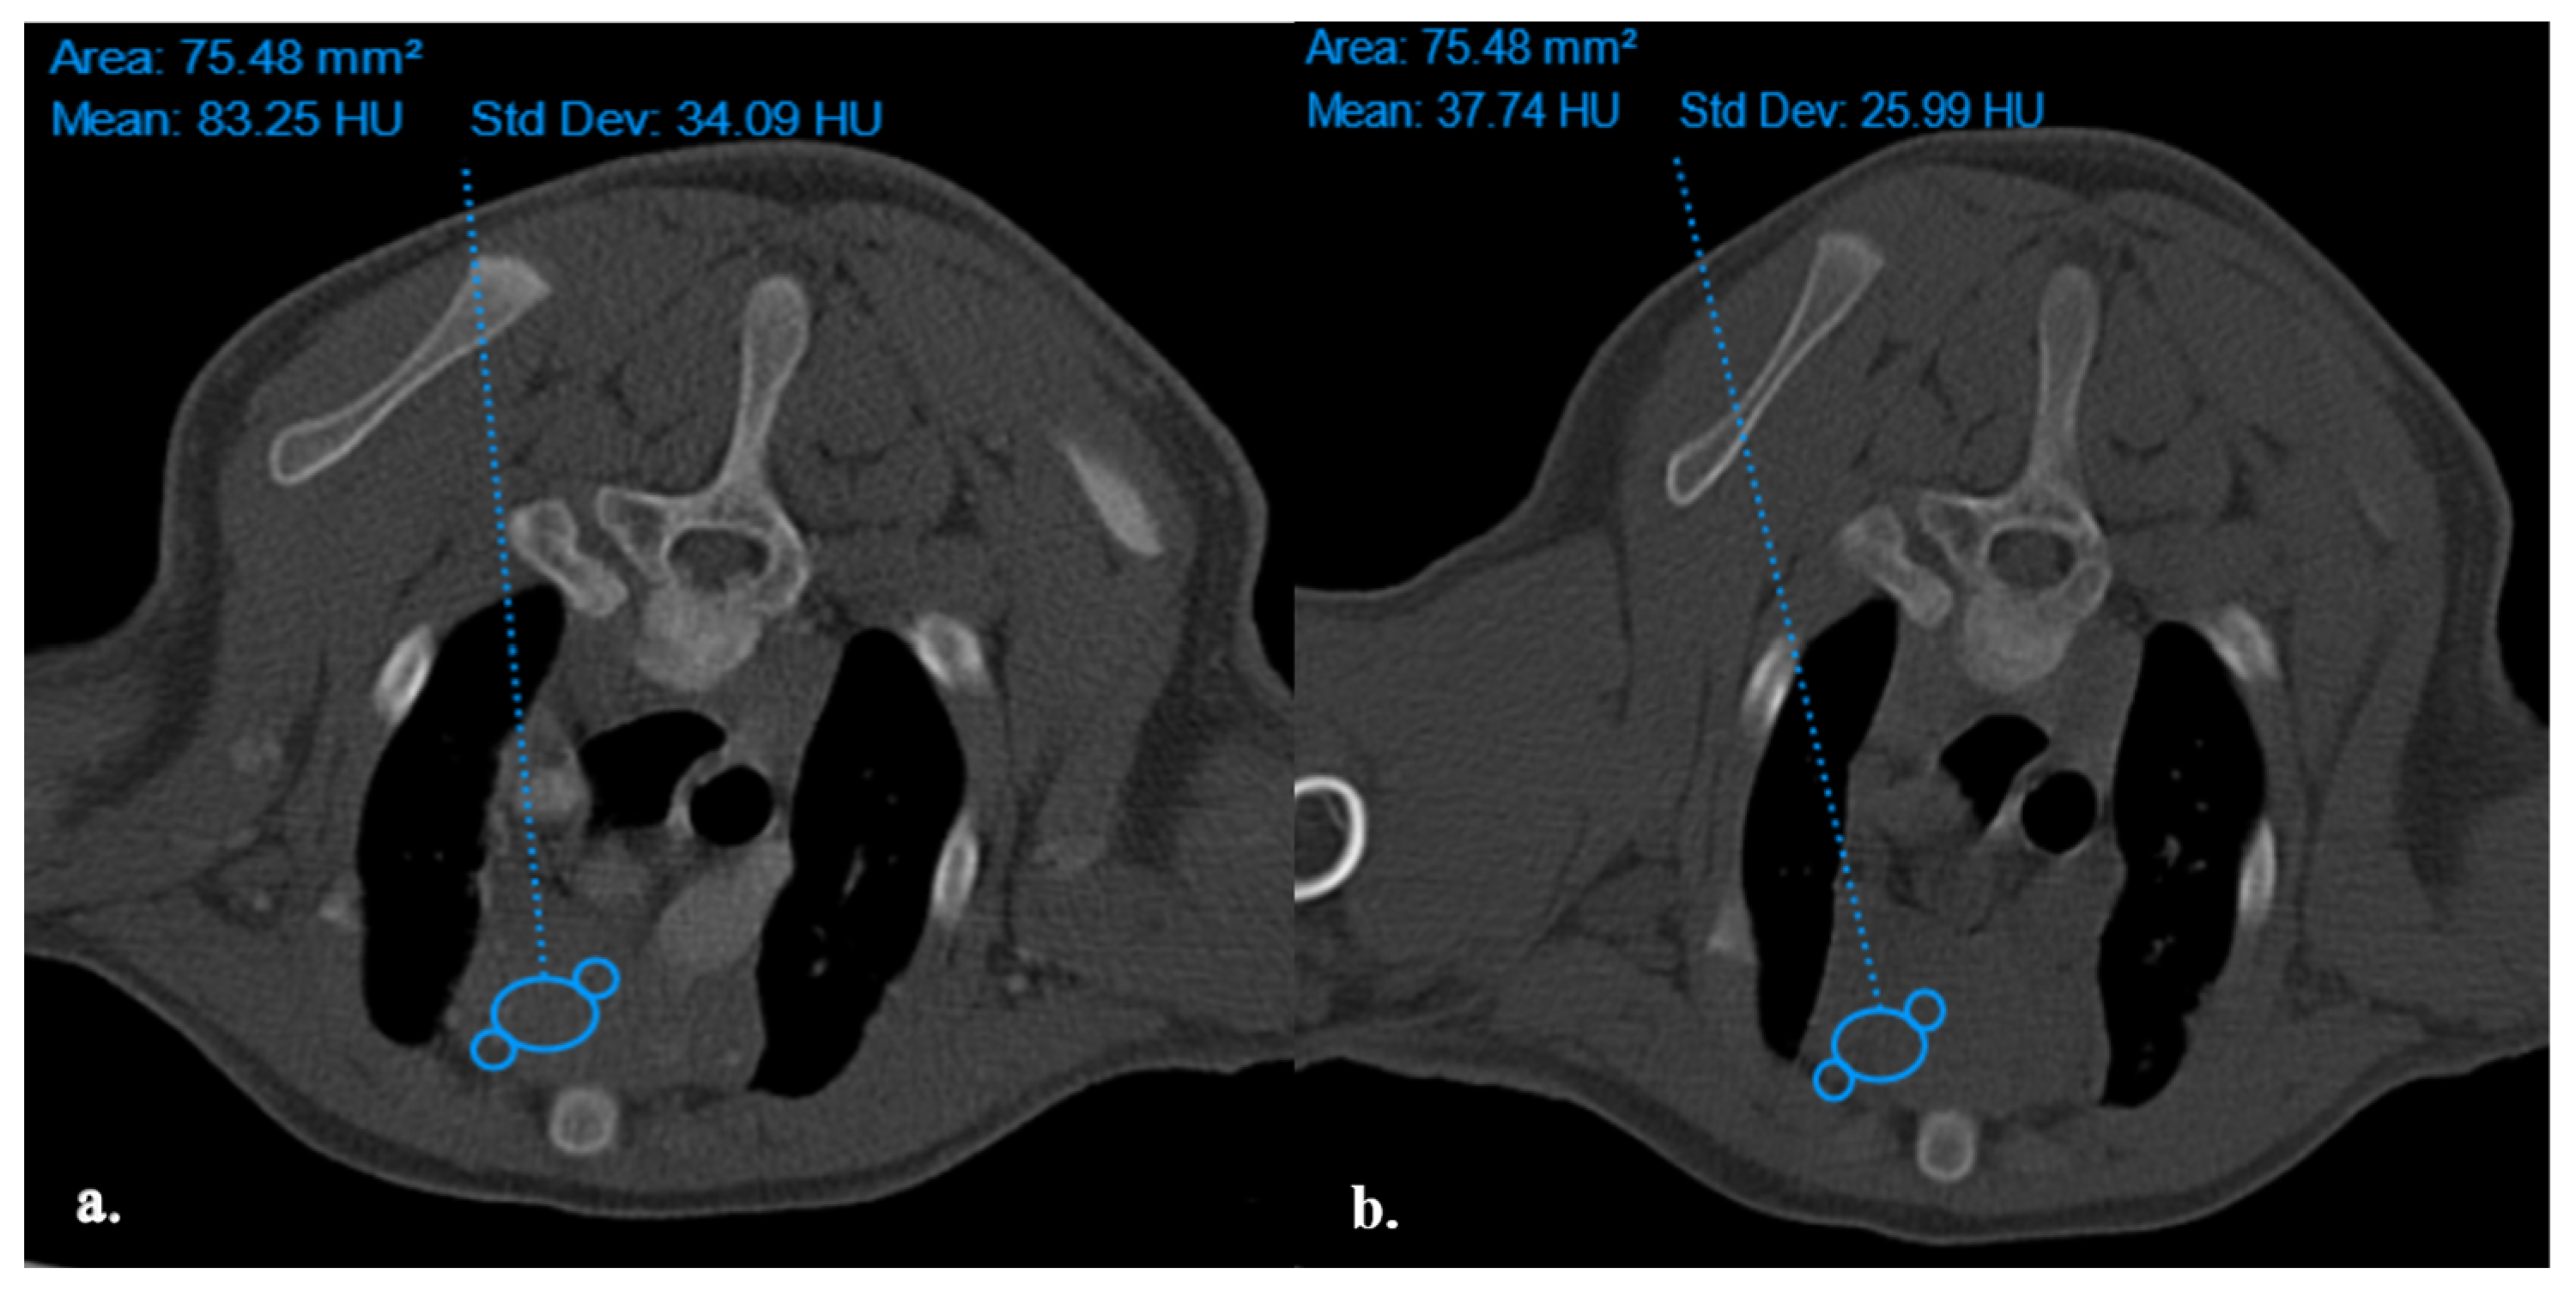

The thymus glands were evaluated in the first step to determine whether they were visible or not. Non-visible thymus glands were those with complete degeneration seen with fat attenuation and not distinguishable from mediastinal fat. After that, a grading system for thymic tissue appearance was used based on its predominant component (grade-0: totally fatty replacement of the thymus (non-visible) and could not differentiate from mediastinal fat; grade-1: more than 50% fatty replacement of the thymus; grade-2: more than 50% soft tissue component in the thymus; grade-3: totally soft tissue component in the thymus (Figure 1). After grading the thymus, the attenuation (CT number) of thymic tissue in plain and contrast-enhanced images was measured. For this purpose, a round-shape region of interest (ROI) with a surface equal to 75 mm2 was considered in the widest part of the organ for large thymus glands (Figure 2) and a smaller ROI for small thymus glands. Then pre- and post-contrast Hounsfield Units (HU) were compared for each patient individually and also between groups for evaluating the pattern of attenuation alteration.

Figure 2. Density Measurement in ROI equal to 75.48 mm2 in Plain (a) and post-Contrast (b) CT Scan Examinations of a four-month Mixed-Breed Male Dog with a Visible Grade 1 Thymus. The Thymus is Rectangular Shape with one Convex Border and is located in the midline position.